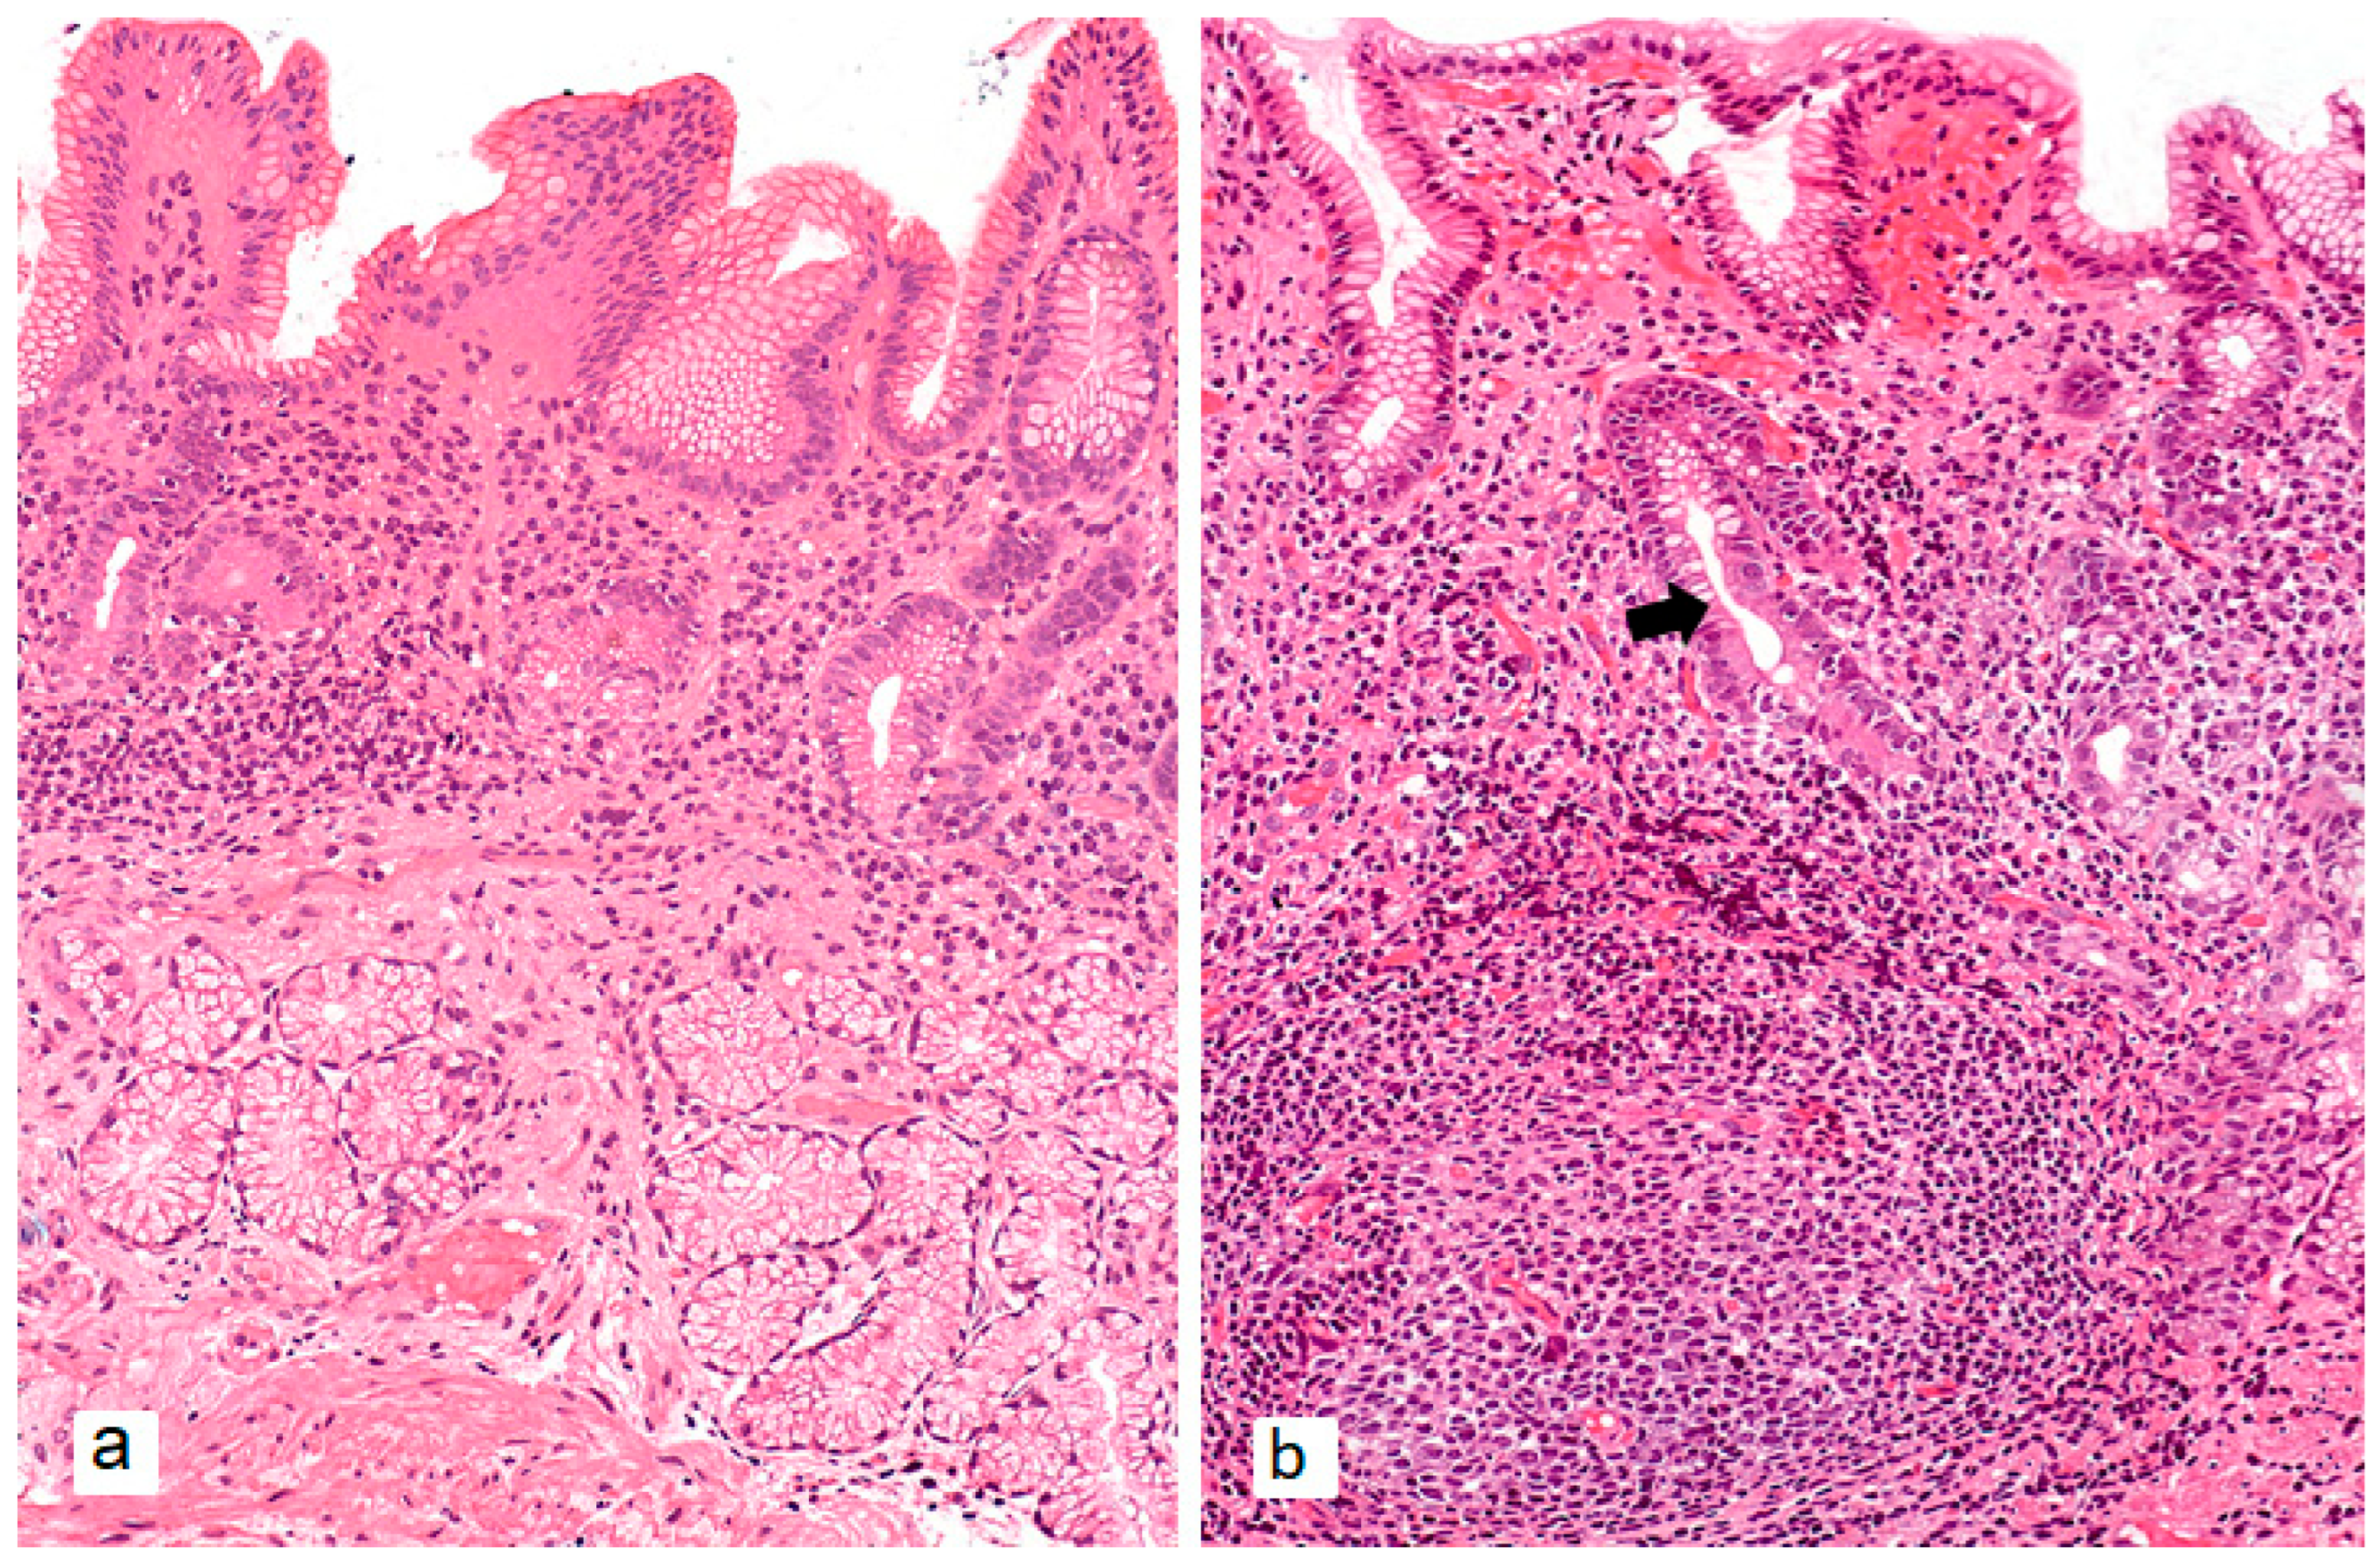

- Rugge, M.; Fassan, M.; Pizzi, M.; Zorzetto, V.; Maddalo, G.; Realdon, S.; De Bernard, M.; Betterle, C.; Cappellesso, R.; Pennelli, G.; et al. Autoimmune Gastritis: Histology Phenotype and OLGA Staging. Aliment. Pharmacol. Ther. 2012, 35, 1460–1466. [Google Scholar] [CrossRef]